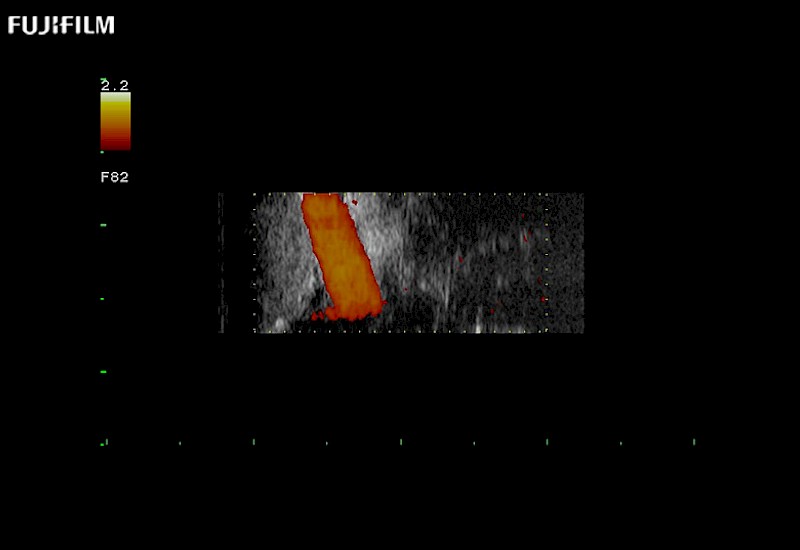

Extraordinary high-resolution digital imaging

Multi-Parametric imaging modalities

Our dedication to neurosurgery allows us to offer superior image quality, outstanding system reliability and intuitive use of cutting edge technology.